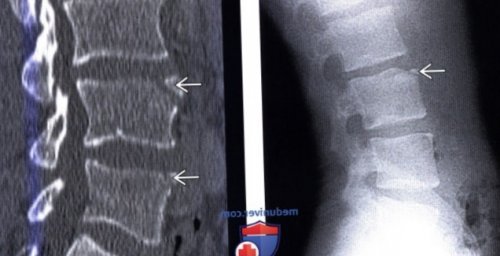

прогноз:апофизом тела позвонка (Справа) Сочетание limbus vertebra

одном уровне. Обратите внимание на

с LV на

vertebra у L4

(Справа) КТ, сагиттальная проекция: типичные фрагменты limbus

и L5 — типичная картина несросшегося

(Справа) КТ, сагиттальная проекция: четко отграниченные костные